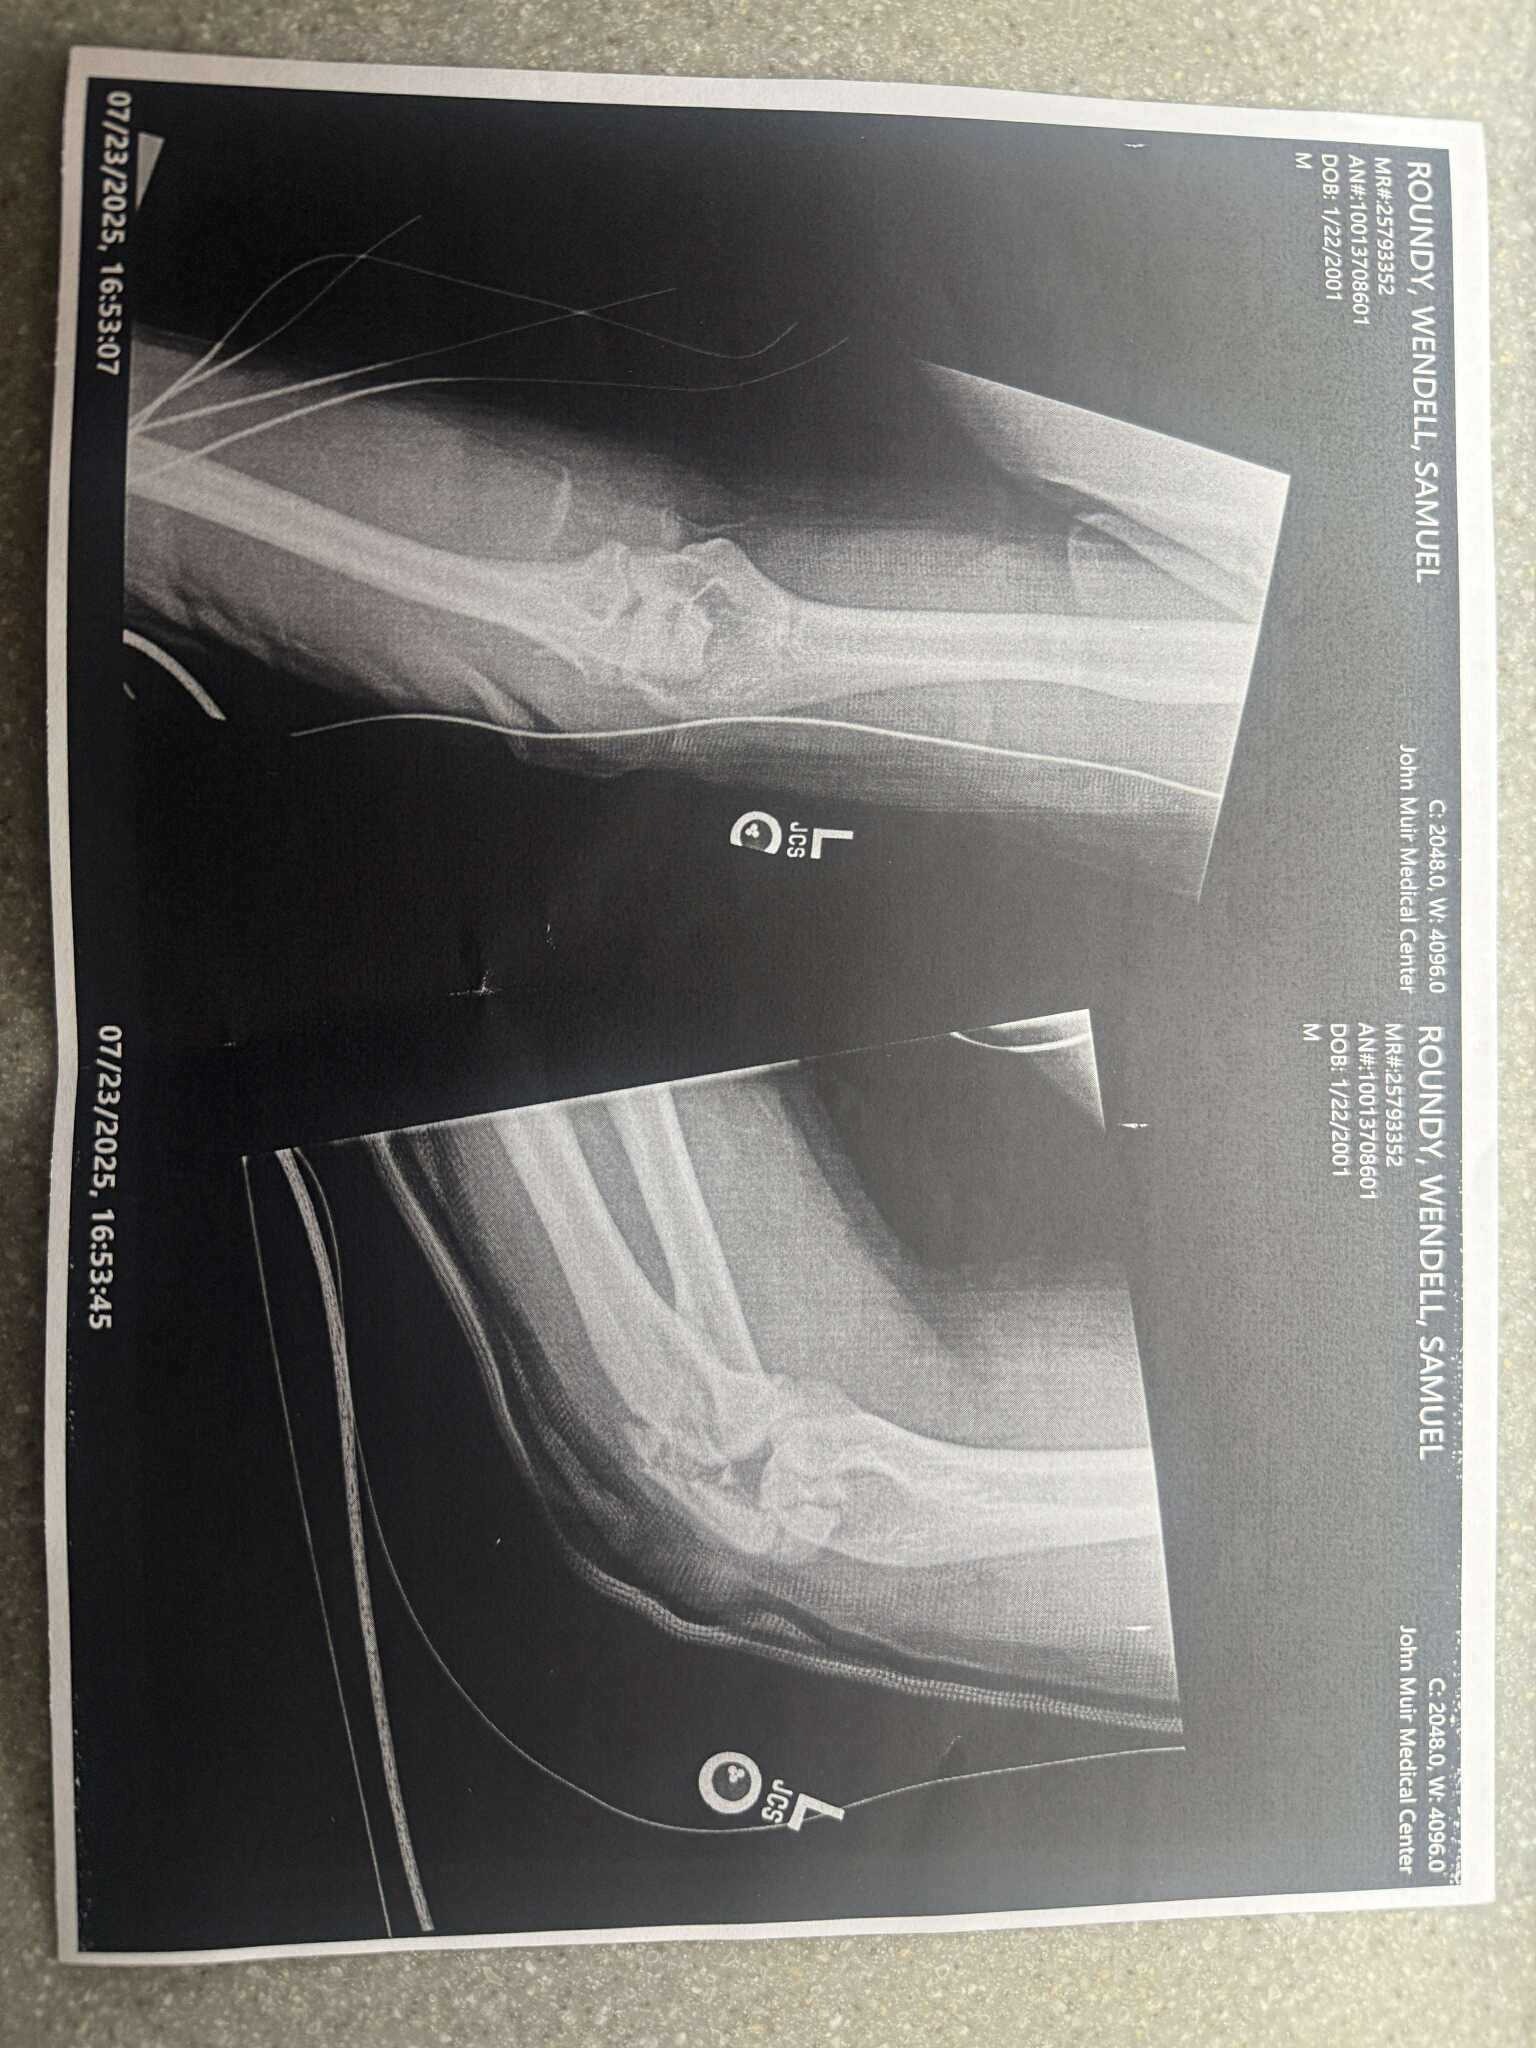

He has suffered serious injuries; his elbow is shattered, his hip is broken, his femur is broken, and the lower part of his left leg is severely damaged. He’s had three major surgeries so far, one to place a rod and screws from his hip to his knee, and another to repair one of three main arteries in his leg due to them being torn. Unfortunately, when doctors went in to repair his main arteries, they found them all to be shredded, so they could only save one. And the most recent surgery was to determine his muscle and nerve condition, which they found to be in critical condition.